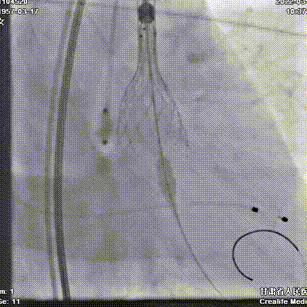

主动脉根部造影

瓣叶增厚,中度反流

TaurusAtlas 20mm球囊预扩

冠脉灌注良好,无腰征